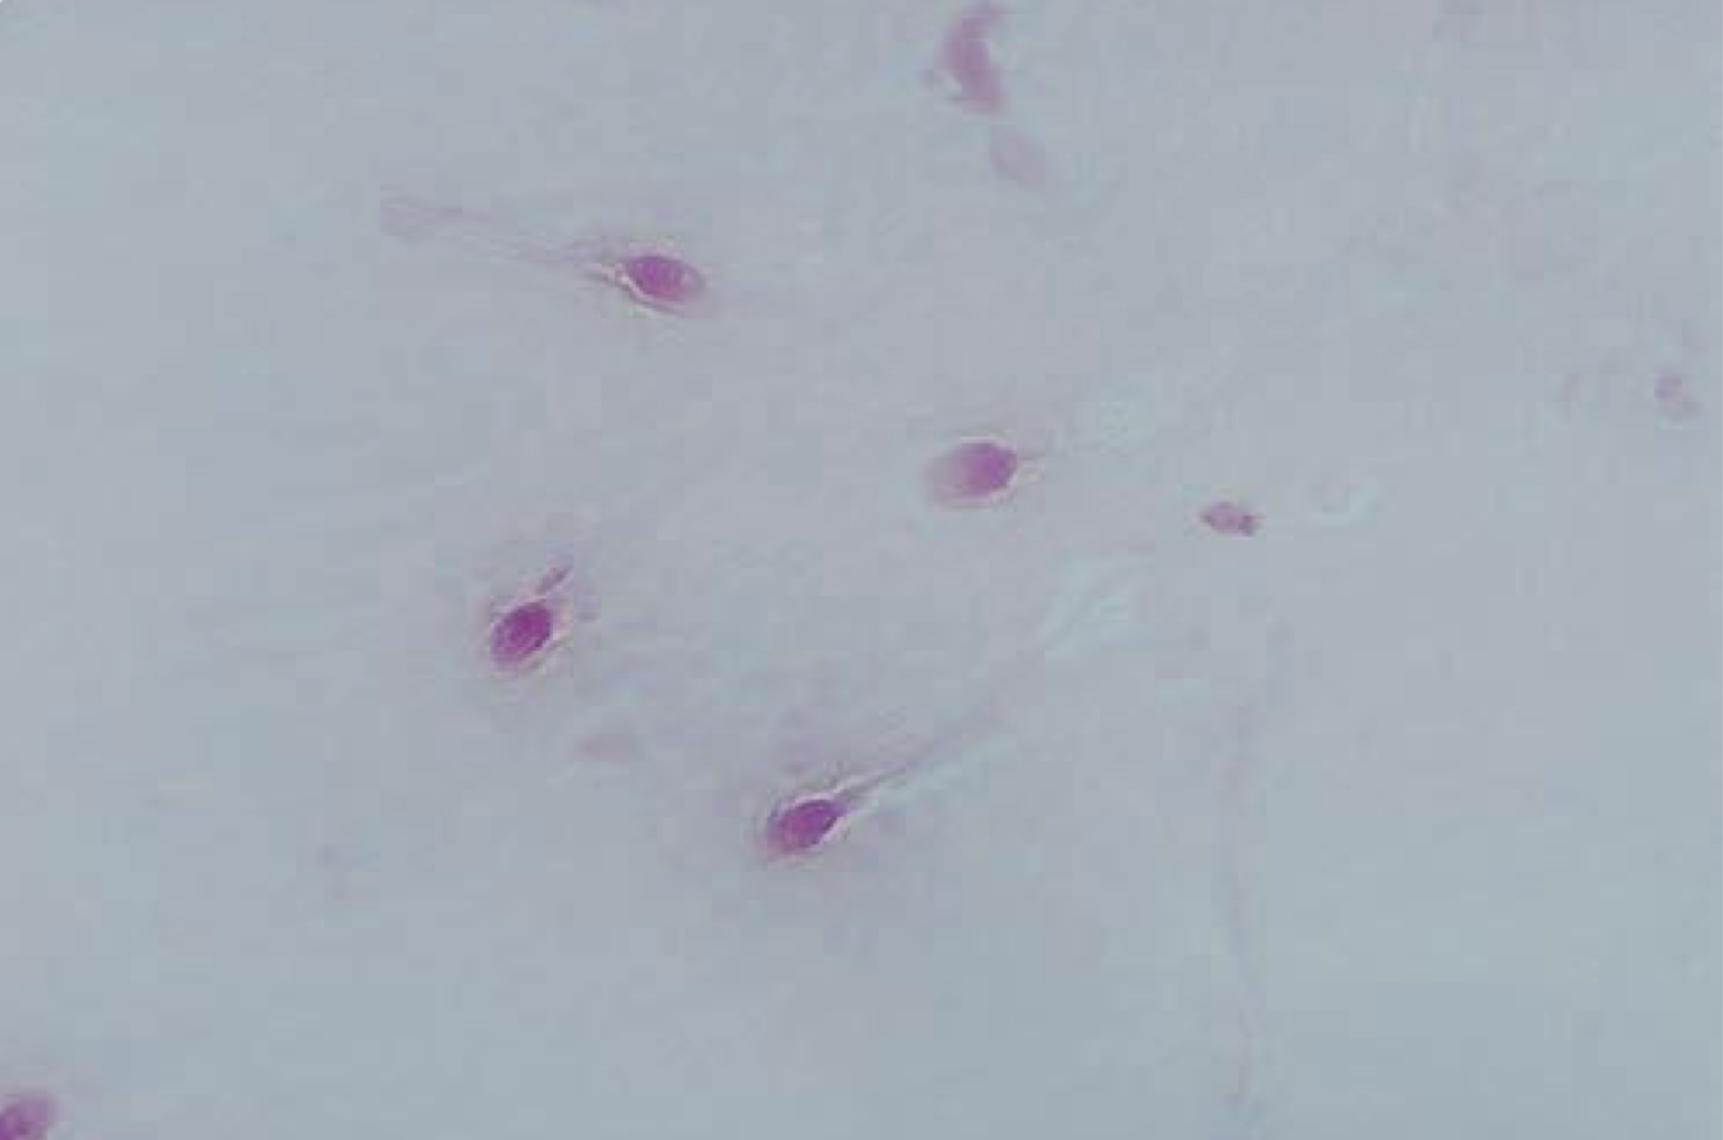

Nonviable spermatozoa